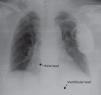

A chest X-ray showed that the generator had rotated and that both leads had become displaced, with the atrial lead situated in the left subclavian vein (Figure 2). Surgery was performed to reposition the ventricular lead and to replace the atrial lead with an active fixation lead (Figure 3); the generator was attached to the pectoral muscle. Subsequent follow-up was unremarkable.